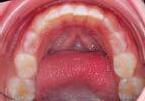

Andréa Case treated with EF Kid

Treatment time: 24 months

• Maxillary left endoalveolia • Severe dental crowding

Wearing of EF Kid for 12 months

7 y.o.

Results: Closure of open bite • Improved arch rounding

… then with EF T Slim

Wearing of EFT Slim for 12 months

Results: guiding of adult teeth